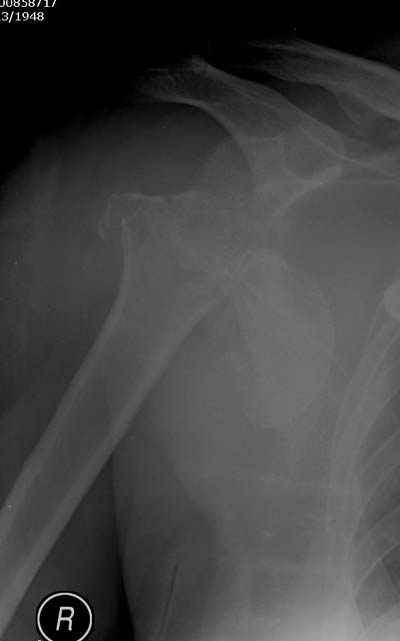

Спасибо за участие в дискуссии -перелом шейки плеча, для себя я прояснил многие технические моменты...

Посылаю послеоперационные Рг граммы.

Поздравляю, получилось просто замечательно. Если можно, расскажи чуть подробнее, как делали - как вправляли, как вводили спицы, поворачивали ли их?

Спасибо за поздравления:-))

Я и сам доволен результатом. В предпоследнем письме я кратко описал ход операции - закрыто репонировать не удалось( 2 недели с момента травмы и 1 неделя после неудачной репозиции) после удаления пучков спиц, пришлось сделать - 2см разрез на уровне перелома и с помощью периостального элеватора (золотое правило механики) *одеть* головку на дистальный отломок.

Спицы проводил через старые отверстия, вращая пучок импактором- направителем при его введении в головку.